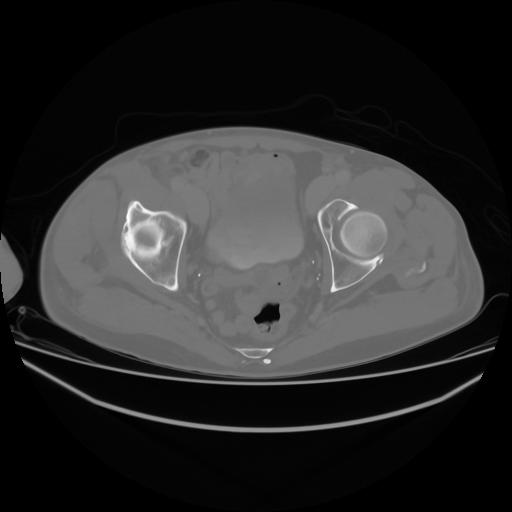

4 CUERPO,CE,Axial,3.0,CUERPO,,